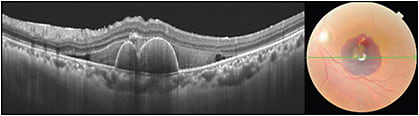

Pigment epithelial detachments (PED) can often appear optically empty on conventional SD-OCT images, whereas with EDI-OCT, the contents of the PED can be better visualized.9 Using EDI-OCT, Spaide et al were able to demonstrate the choroidal neovascularization within the PED as a hyper-reflective layer of tissue under the back surface of the RPE (Figure 2).10